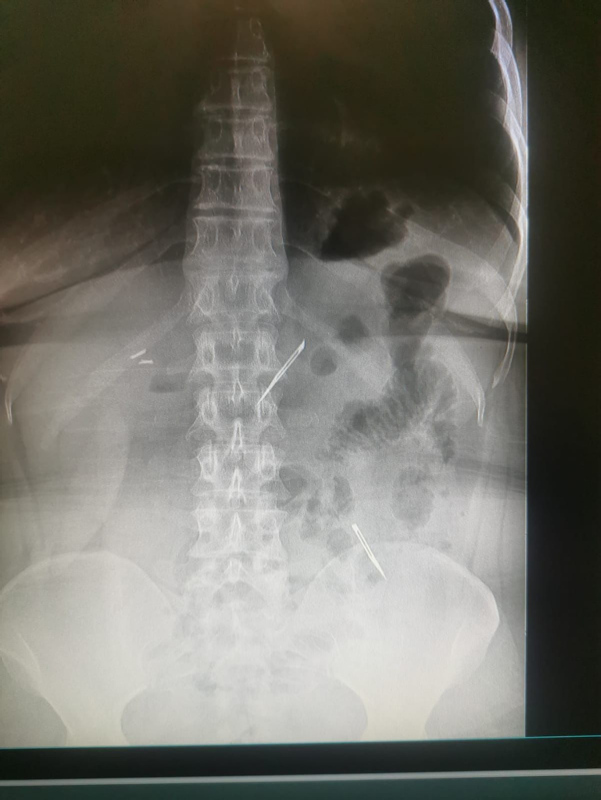

Sağlık Bilimleri Üniversitesi Ankara Atatürk Sanatoryum Eğitim ve Araştırma Hastanesi'ne mide ve karın bölgesinde aşırı ağrı şikayeti ile müracaat eden 46 yaşındaki D.E.'nin yapılan tahlil, tetkik ve çeşitli görüntülemelerden sonra bağırsak kısmında 2 adet neşter olduğu tespit edildi.

Genel cerrahi kliniği tarafından zorlu bir ameliyat sonrasında neşterler kadının vücudundan çıkarıldı.

Ameliyatı gerçekleştiren Sağlık Bilimleri Üniversitesi Ankara Atatürk Sanatoryum Eğitim ve Araştırma Hastanesi Genel Cerrahi Kliniği Eğitim ve İdari sorumlusu Prof. Dr. Hakan Buluş ise hastanın yoğun şikayetleri üzerine çektikleri röntgen sonrasında 2 adet neşteri görünce şaşkına uğradıklarını söyledi.

Detaylı inceleme sonucunda bu cisimlerin neşter olduğunu fark ettiklerini belirten Prof. Dr. Buluş, "2 adet yabancı cismin bistüri (neşter) ile uyumlu olduğunu gördük. Bunun üzerine hastanın şikayetlerinin de artması üzerine, ameliyat kararı verdik." şeklinde konuştu.

"AMELİYATLARDA KULLANDIĞIMIZ..."

Çıkardıkları cismin, neşterin normalde ameliyatlarda kullanılan bir malzeme olduğunu söyleyen Prof. Dr. Buluş, "Çıkardığımız yabancı cisimler bizim ameliyatlarda sıkça kullandığımız 11 numara dediğimiz bir bistüri tipi. Ebatları da yaklaşık 4 santime yarım santim ebatlarında." diye konuştu.